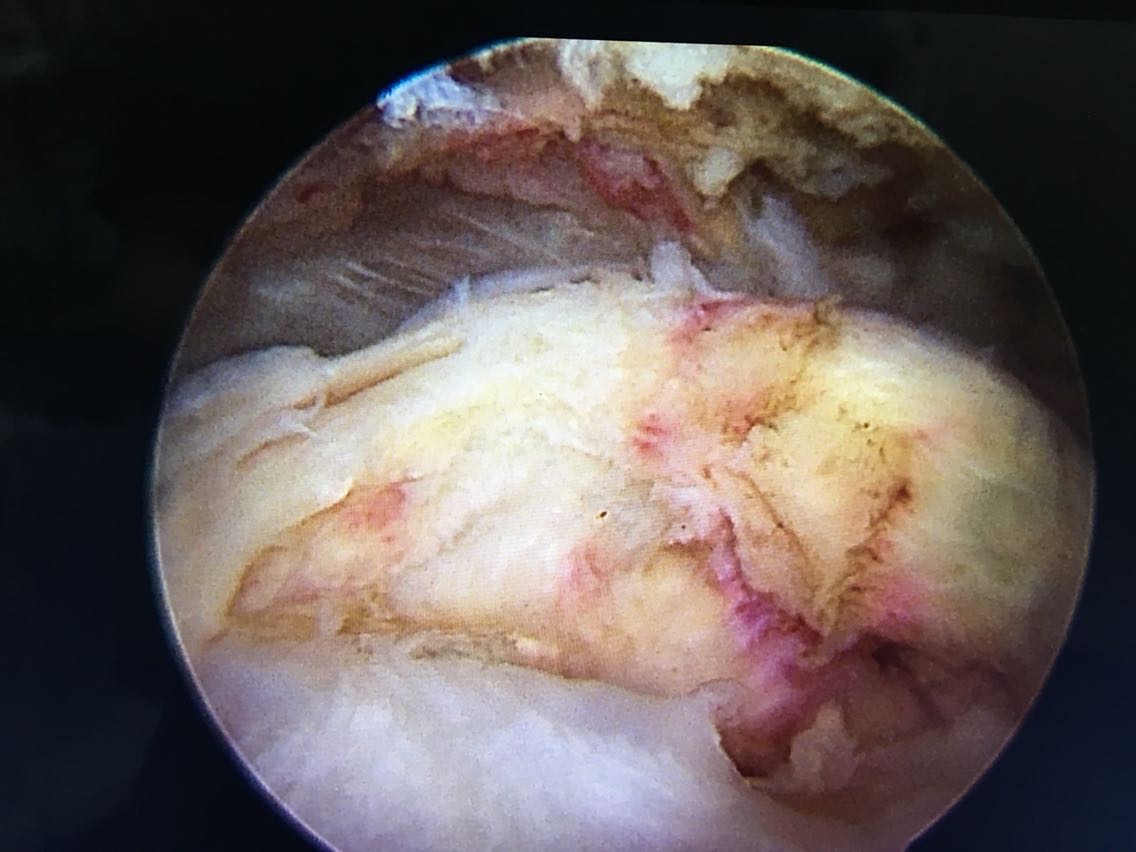

诊断:右肩袖撕裂 肩峰撞击症 冻结肩 治疗:关节镜下清理 肩峰撞击成形 肩袖撕裂修补手术。